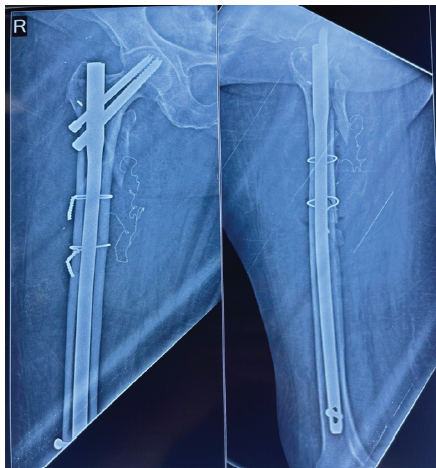

Pus culture from her previous hospital reports showed growth of Escherichia coli sensitive to Amikacin and Tigecycline. Plain radiograph of the thigh showed a tortuous, crumpled X-ray detectable thread, which was suggestive of abdominal mop (Fig. 2).

Figure 2: Post-operative plain radiograph showing tortuous X-ray detectable thread-like material medial to the proximal femur.